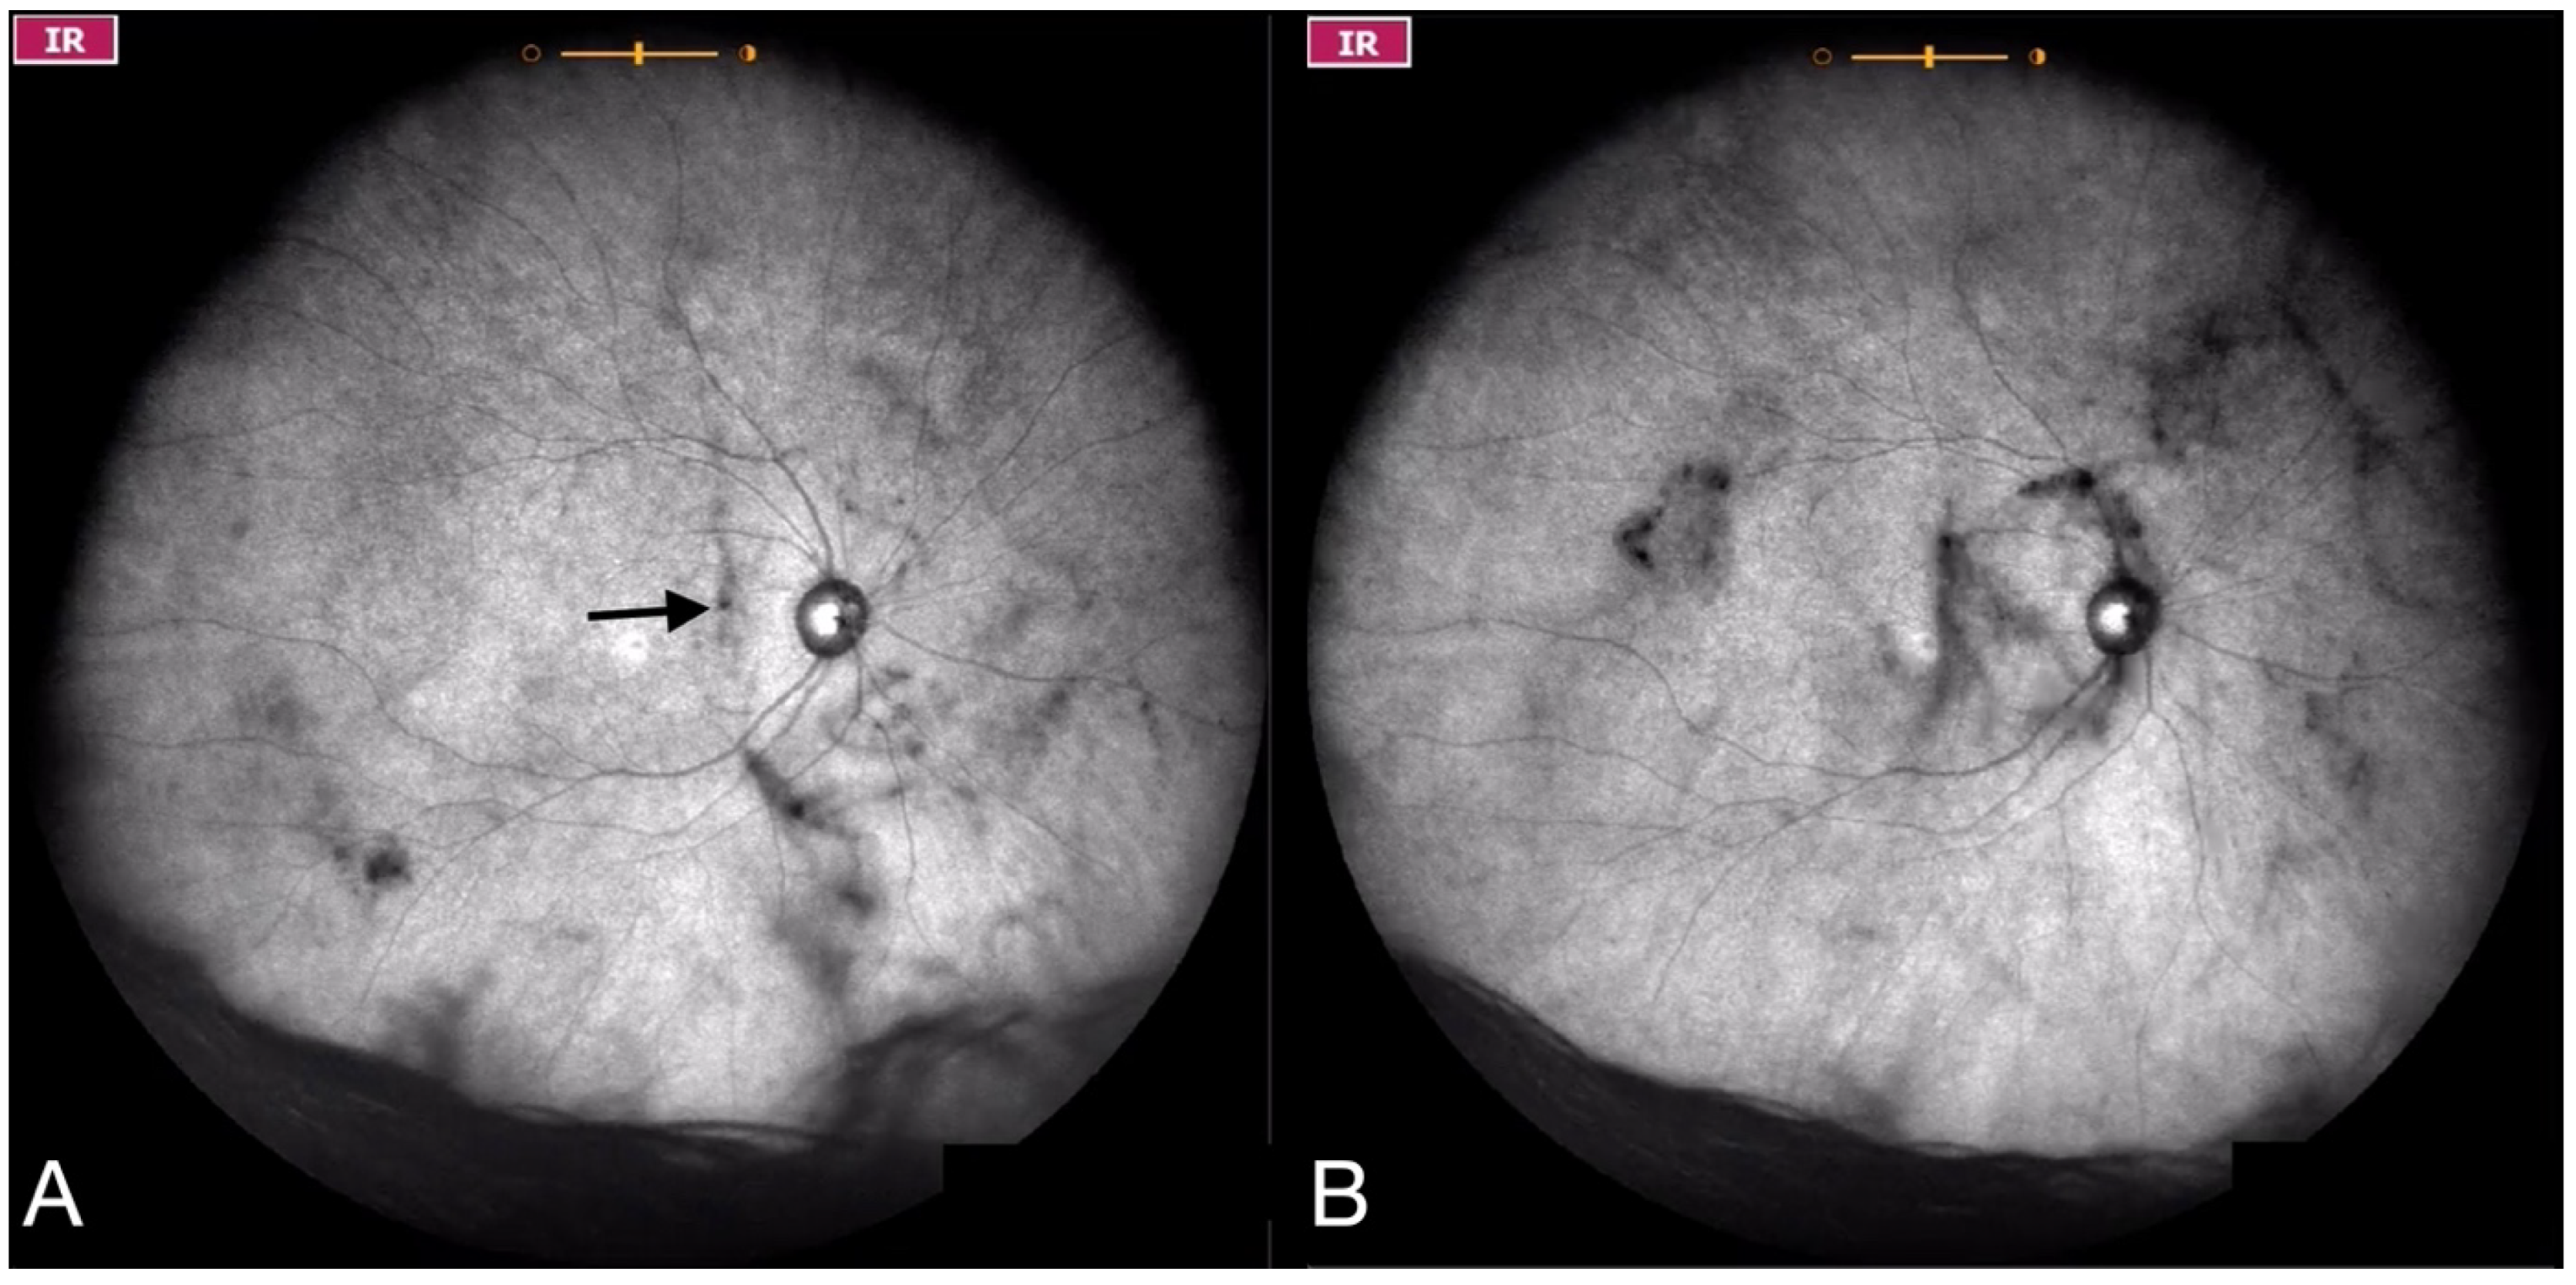

| Grade 4—Dense opacities that involve the center of the macula in the primary gaze (Figure 6 and Video S6). |